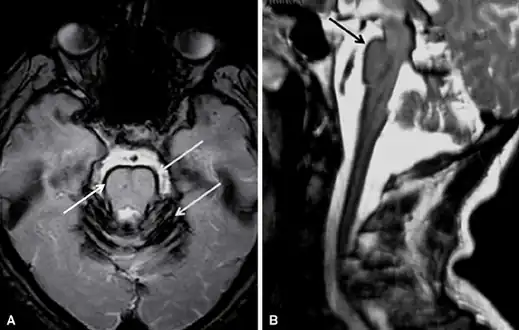

Early detection of superficial siderosis is usually via MRI. The iron deposition that is characteristic of superficial siderosis shows up as a hypointense band in affected tissues, with a characteristic rim of intensity appearing on the cerebellum; a hyperintense rim is rarely seen.[8] Taking samples of cerebrospinal fluid may also reveal siderosis through xanthochromia, elevated presence of red blood cells, high iron and ferritin concentrations, and elevated levels of the proteins Tau, amyloid beta (Aβ42), neurofilament light chain (NFL), and glial fibrillary acidic protein (GFAP), but the CSF is sometimes normal.[10] Detection is complicated by the fact that superficial siderosis is a rare disease and is not well described in neurological texts, so it may go unnoticed until noticeable symptoms appear.[11]

Brain MRI of a individual with superficial siderosis

Brain MRI of a individual with superficial siderosis MRI showing pulsations of CSF (normal individual)